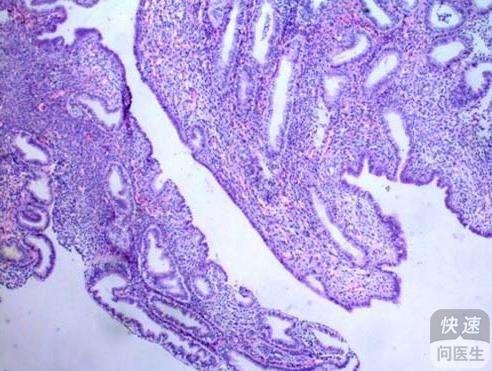

对于子宫内膜间质肉瘤这类疾病来说,积极的进行检查、诊断和治疗都是非常重要的,现如今常见的检查子宫内膜间质肉瘤的方法包括B超检查、彩色多普勒测定、术前诊刮和实验室检查等,医生则需要根据患者的检查结果来进行...